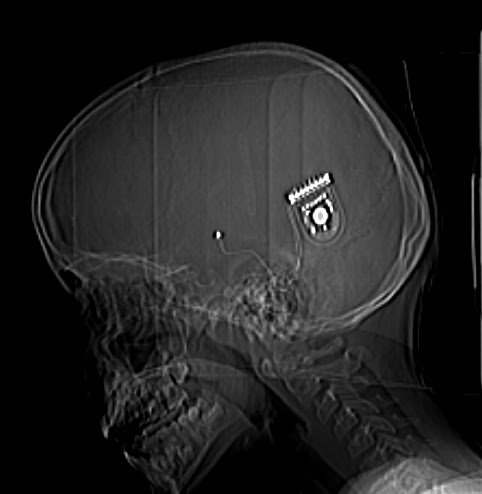

I think most of us have had an ear infection, an ice cream headache, or sore ears after a rapid descent from a long flight. This feels like all three, but localised in the left side of my head. When I turn my head too much to the right, pain shoots down the side of my neck. It’s not agonising. Just a dull ache that’s always there. Strangest of all, when I turn my head a certain way, I can feel the skin stretching over something foreign – a magnet and a tiny circuit board that is now inside my head for the foreseeable future.

At the same time, I’m wondering how life will be now I have this tiny magnet, circuit board and electrode permanently stuck inside my head. I definitely feel different right now, and I sort of miss the old, relatively undamaged, complication free, pain free, side effect free Billy 1.0. I can’t do a system restore to my old self. Whoever I was before – physically at least – is now gone for ever and I have to live life as I am now.